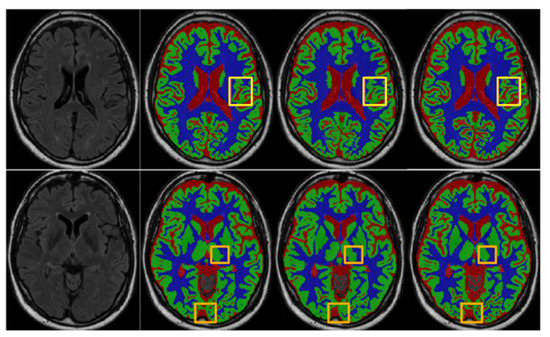

4.1. Ablation for Multi-Branch Pooling (MP)

4.2. Ablation for Multi-Branch Output with Multi-Branch Dense Prediction (MDP)